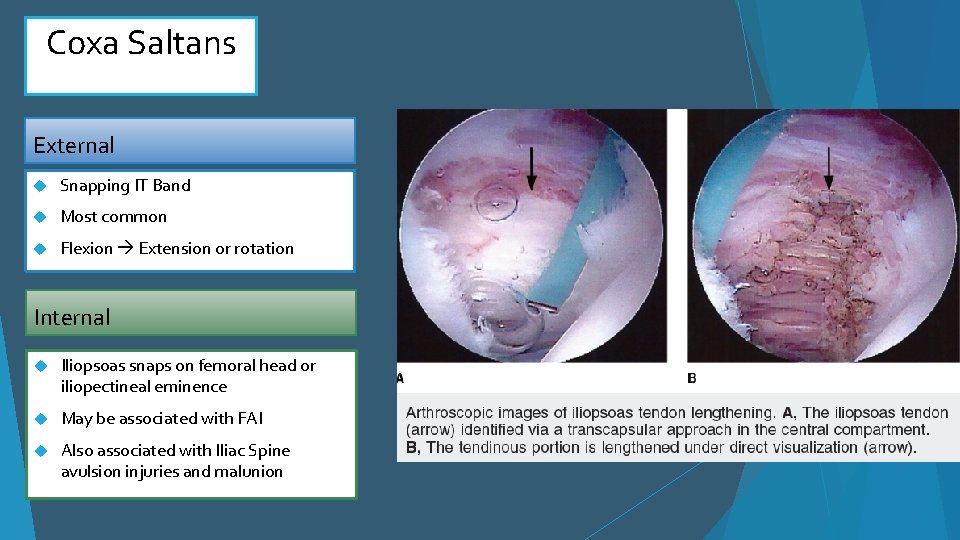

Coxa Saltans External Snapping IT Band Most common Flexion Extension or rotation Internal Iliopsoas snaps on femoral head or iliopectineal eminence May be associated with FAI Also associated with Iliac Spine avulsion injuries and malunion